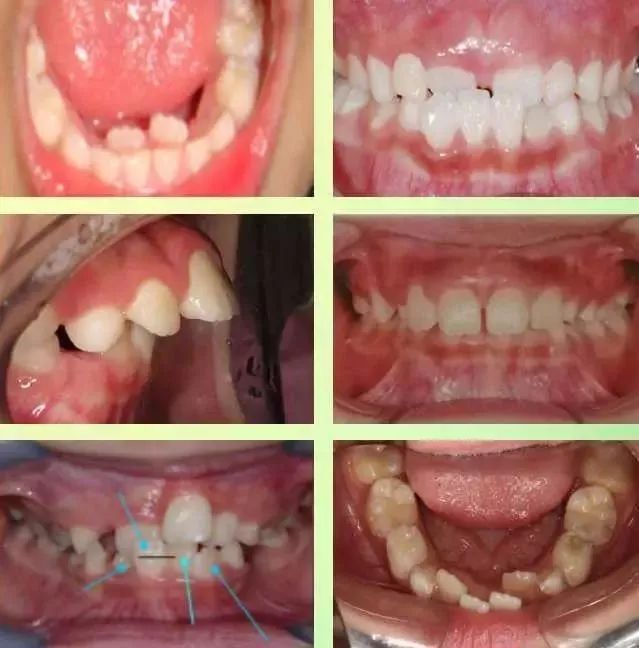

我哋睇一組相

喺小朋友生長早期,因為小朋友嘅壞習慣,容易出現齒唔齊,深覆合,地包天等口腔問題。

牙齒唔齊係指細路成長發育過程中,由天生嘅遺傳因素或者後天嘅環境因素導致嘅牙齒排列唔齊、上下牙弓牙頜關係異常、頜骨大小形態位置異常、面部畸形等問題。有以下幾個情況你要留意下。